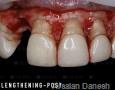

Pictures

Surgery